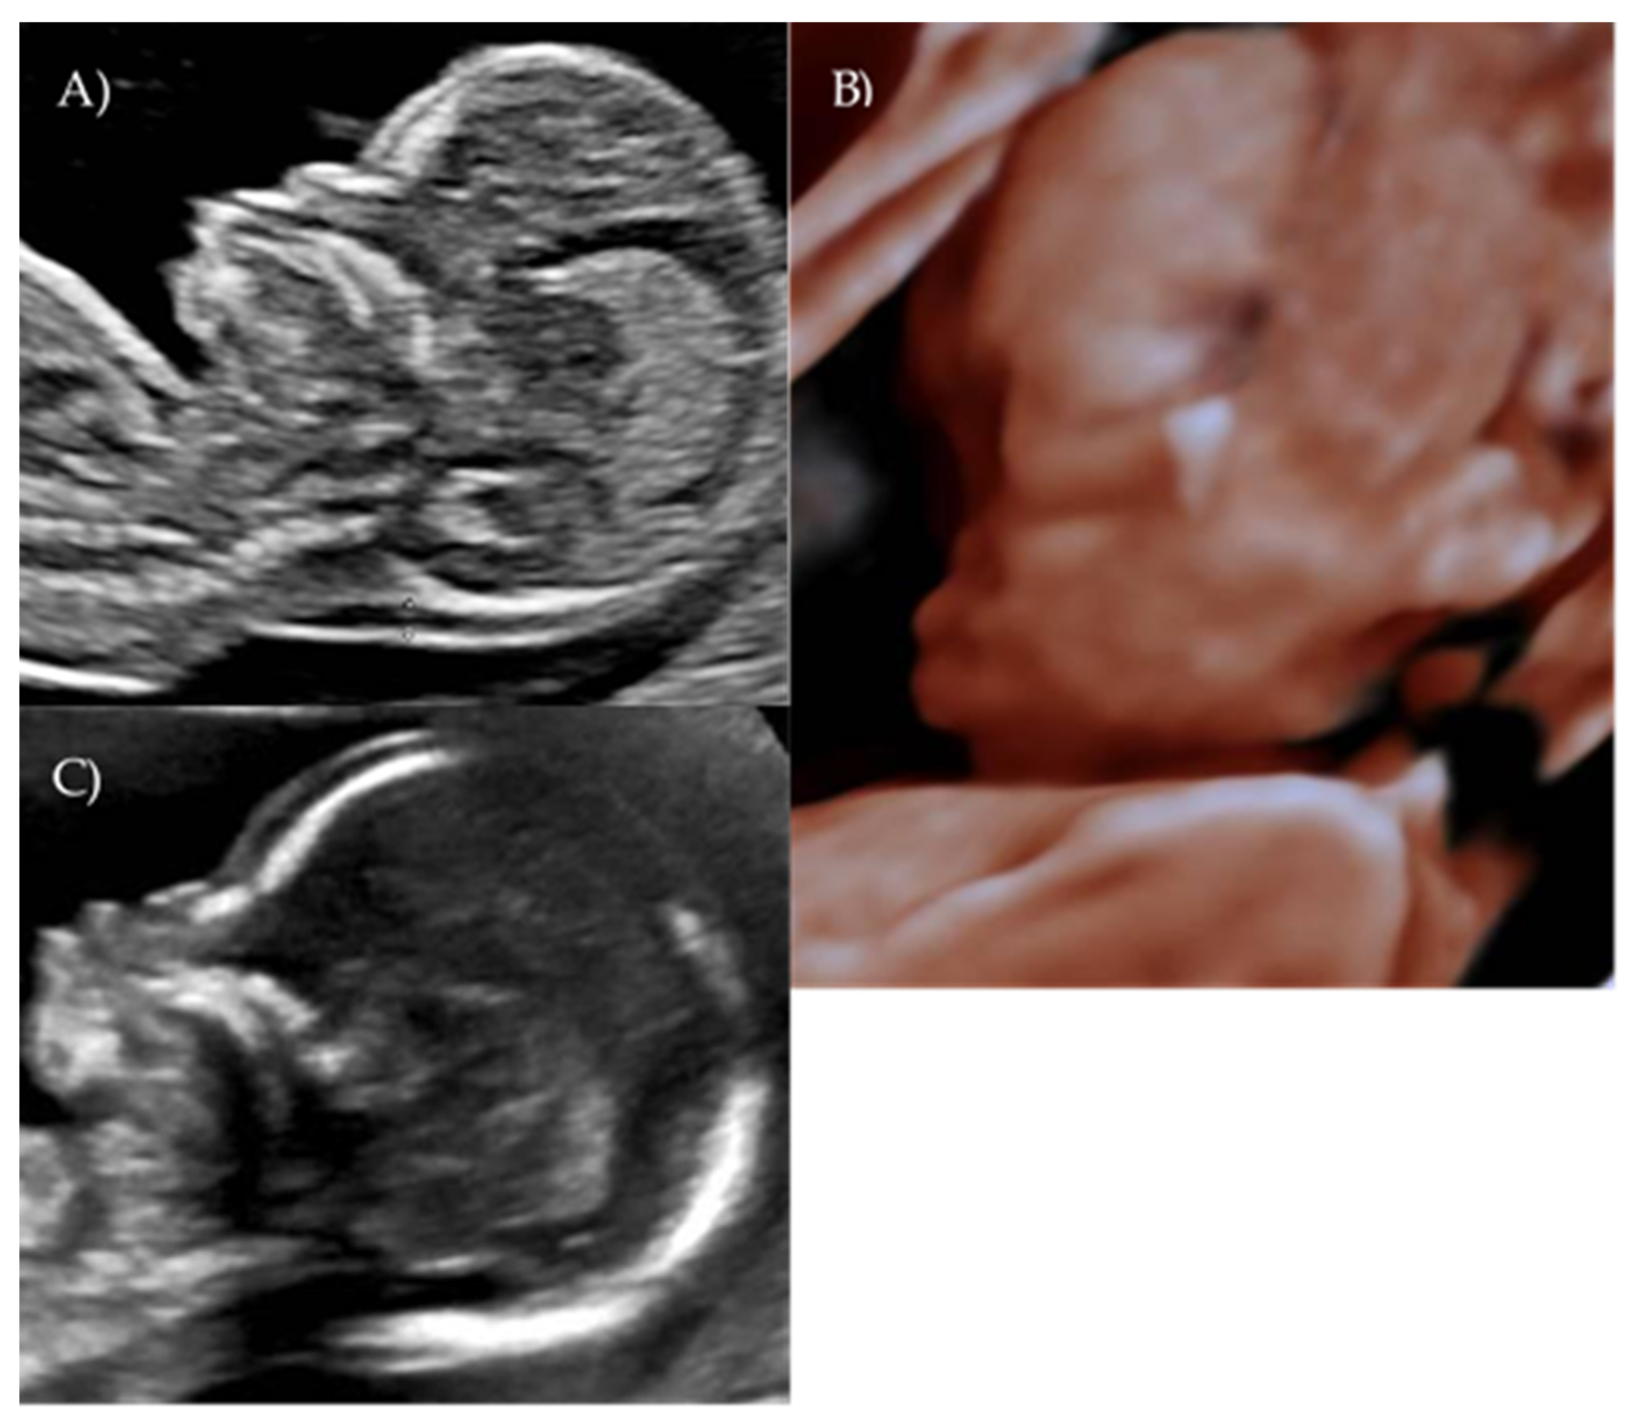

During the first-trimester scan a flat fetal profile was noted and suspected of indicating a fetal abnormality, and early re-evaluation of the fetal craniofacial anatomy was recommended (Figure 2A).

At 17 weeks and 4 days of gestation, follow-up ultrasound confirmed a flattened fetal facial profile consistent with Binder-type maxillonasal dysplasia (Figure 2B,C). Other fetal anatomy findings appeared normal.

Figure 2. Case 2. (A) First-trimester 2D ultrasound fetal profile. (B) Flat fetal profile, 3D reconstruction, at 17 + 4 w. (C) Flat fetal profile, 17 + 4 w.